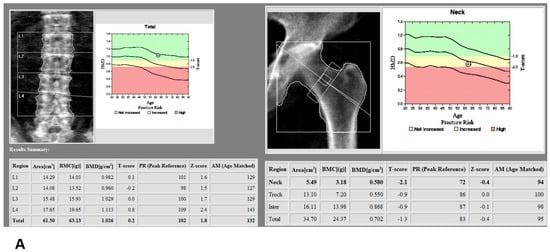

A total of 125 patients who underwent TKA between November 2021 and January 2022 and had both preoperative third-generation dual-source DECT and DXA within three months before surgery were considered for study inclusion. The study was approved by the Institutional Review Board of our institute (PC22RISI0049) and it was exempted from informed consent because it is a retrospective medical and radiological record review. Patients with metal prosthesis, fracture or infection in central (spine or hip) or peripheral (distal femur or proximal tibia) regions were excluded (Figure 1). DXA at the lumbar spine and left pelvic area had been taken within 3 months before TKA (Figure 2A), and had identified osteoporosis in 11% of L2 vertebral bodies and in 14.5% of femur necks (Table 1). Lower extremity CT was performed for the purpose of preoperative planning for TKA with a measured resection technique. All CT studies were performed on a third-generation dual-source CT system in dual-energy mode (SOMATOM Force; Siemens Healthineers, Erlangen, Germany), with tube A at 90 kVp and 180 mAs and tube B at Sn150 kVp [0.64-mm tin filter] and 180 mAs. Image series were collected in a craniocaudal direction with the patient in a supine position without administration of a contrast agent. Three image sets, 90 kVp, Sn150 kVp, and weighted average (ratio 0.5:0.5), were acquired in each CT examination to resemble the contrast properties of single-energy bone CT images. The images were reconstructed with a dual-energy bone kernel (B69f), transferred to the image archiving system (SyngoVia, Siemens Healthineers, Erlangen, Germany), and then transferred to a personal computer carrying the analysis software for postprocessing.

Figure 2.

(A) Assessment of dual x-ray absorptiometry (DXA) in the lumbar spine and femur neck; (B) Manual definition of the region of interest (ROI) and assessment of bone mineral density (BMD) derived from dual-energy computed tomography (DECT) in the distal femur and proximal tibia using dedicated DECT postprocessing software; (C) Manual definition of the region of interest (ROI) and assessment of Hounsfield unit (HU) derived from dual-energy computed tomography (DECT) in the distal femur and proximal tibia using dedicated DECT postprocessing software.